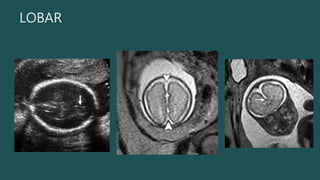

LOBAR

• FISURA

INTERHEMISFERIC

A EN TODA LA

LÍNEA MEDIA

• TÁLAMOS SEPARADOS

• CAVUM SEPTUM PELLUCIDUM SIEMPRE AUSENTE

¿SEMILOBAR O LOBAR?

SI ESTÁ FORMADO EL TERCER

VENTRÍCULO, CUERNOS

FRONTALES Y CUERPO

POSTERIOR DEL C. CALLOSO:

• DX ESPECÍFICO: LÍNEA ECOGÉNICA QUE SIGUE HASTA EL 3ER VENTRÍCULO

• FALTA DE SEPARACION DE LOBULOS FRONTALES POSTERIORES Y PARIETALES

LOBAR • FISURA INTERHEMISFERIC A ENTODA LA LÍNEA MEDIA • TÁLAMOS SEPARADOS • CAVUM SEPTUM PELLUCIDUM SIEMPRE AUSENTE ¿SEMILOBAR O LOBAR? SI ESTÁ FORMADO EL TERCER VENTRÍCULO, CUERNOS FRONTALES Y CUERPO POSTERIOR DEL C. CALLOSO: LOBAR • DX ESPECÍFICO: LÍNEA ECOGÉNICA QUE SIGUE HASTA EL 3ER VENTRÍCULO

• #23 Lobar HPE. (a) Axial US image shows a continuous midline echo anteriorly (arrow). We were not able to demonstrate the cavum septum pellucidum in any plane. (b) Axial fetal MR image shows apparent complete division of the cerebral hemispheres (arrowheads). (c) Coronal fetal MR image shows anterior inferior gyral continuity between the frontal lobes (arrow). This was not demonstrable at US; the index finding was inability to demonstrate a normal cavum septum pellucidum.